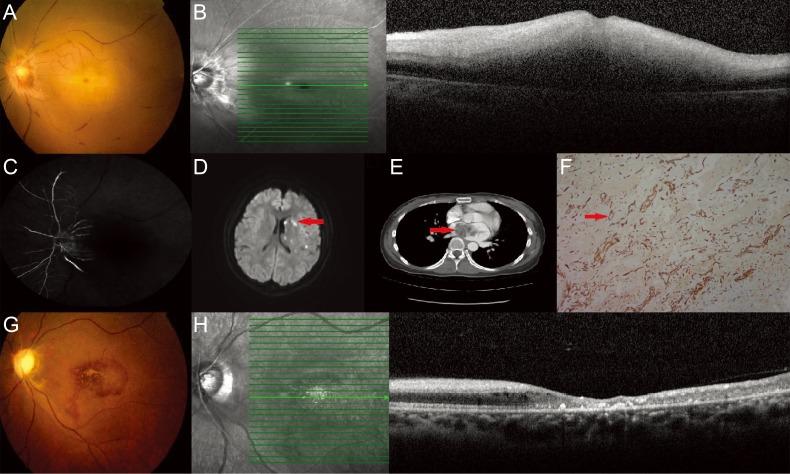

Central Retinal Artery Occlusion by Left Atrial Myxoma.

https://cdn.ncbi.nlm.nih.gov/pmc/blobs/e2a0/5327180/958c32ad804f/kjo-31-88-g001.jpg